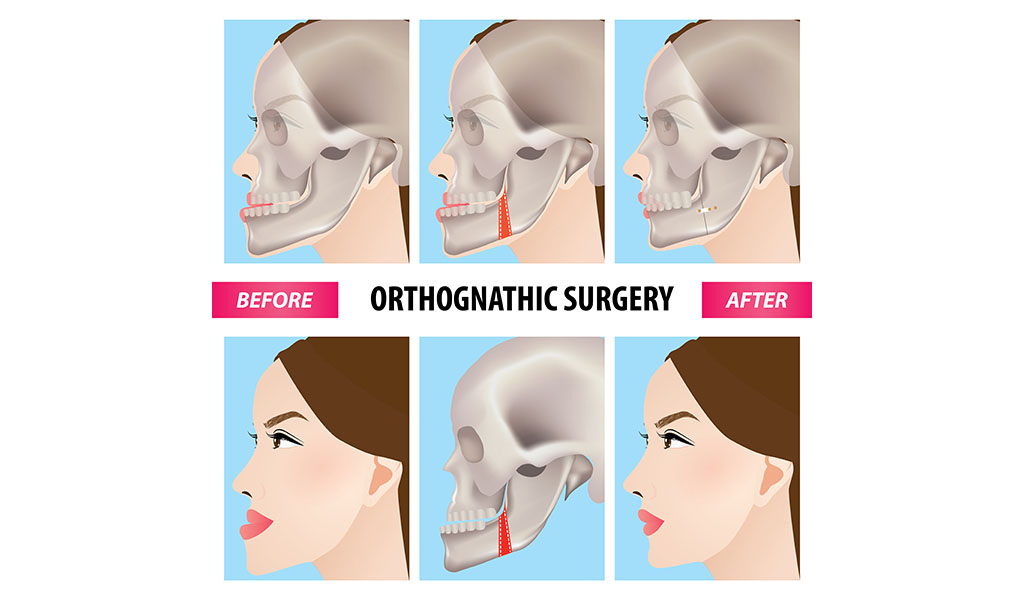

What Is Orthognathic Surgery? - FitBite Orthodontics

www.fitbiteortho.comsurgery orthognathic

www.fitbiteortho.comsurgery orthognathic